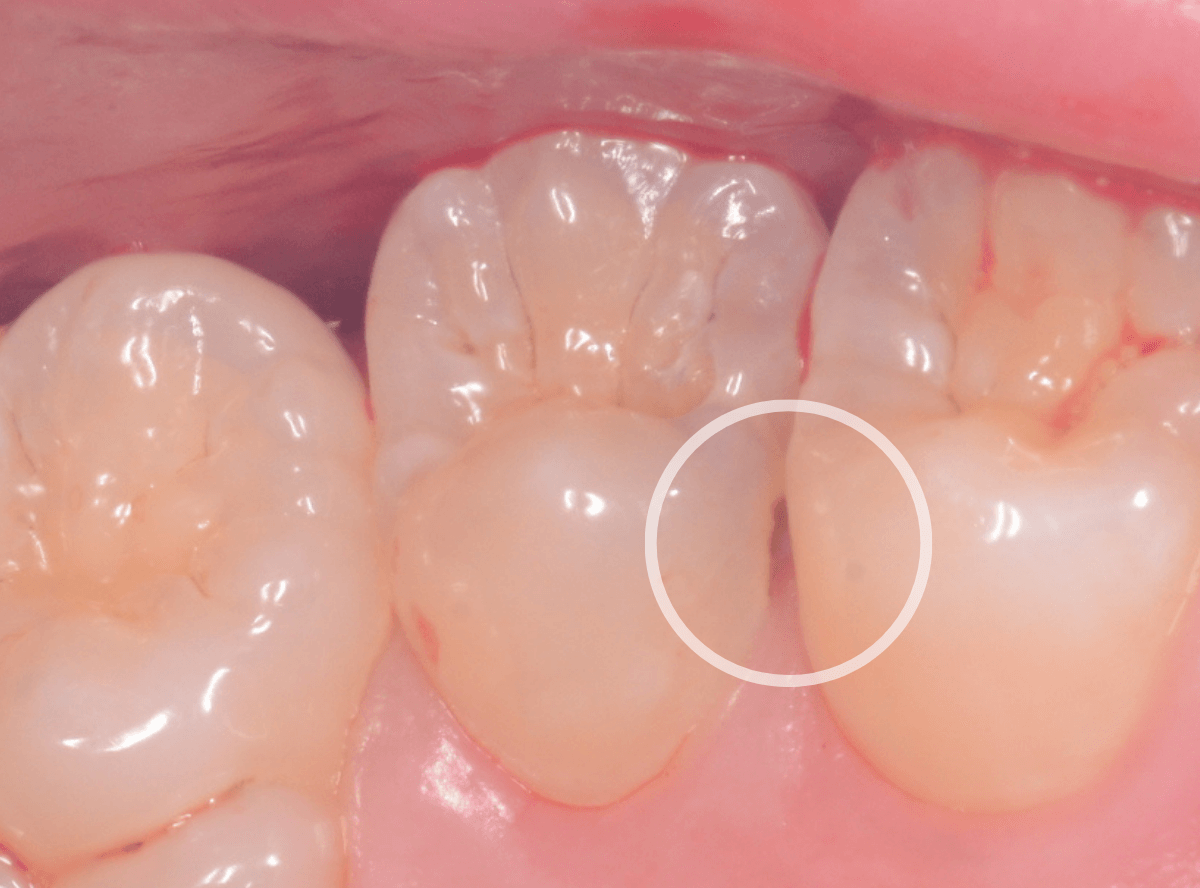

Case.2 メンテナンス時に見つけたわかりづらい虫歯

今回は、定期メンテナンスに通われている患者さんの虫歯を発見したお話です。

定期メンテナンスの際に、歯と歯の境界部分から虫歯のような所見がみられました。

写真でも薄暗くなっているのがわかると思います。

角度を変えて歯の根元の方を観察すると、やはり虫歯がありそうな所見です。

拡大してみると、やはり怪しいです。

レントゲン撮影をして、確認しました。

・・・が、レントゲン上では、虫歯ははっきりわかりません。

患者さんにお話しして、歯を削りながら虫歯を確認します。

やはり、虫歯が出てきました。

結局、少し歯の中まで入り込んだ虫歯でした。

こんな時でも、レントゲン写真で虫歯が確認できない事があります。

今回は、歯科用レジンで虫歯を削った部分をお直ししました。

定期メンテナンスに来院いただき、症状がない状態で虫歯を発見した事で、最小限の治療ですみました♪

皆さんも、治療後のメンテナンスにはお越しくださいね。